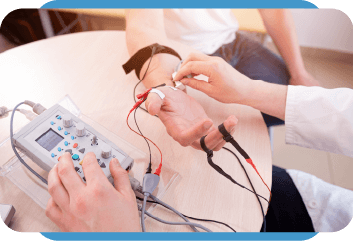

Tecnologia avançada para um diagnóstico mais preciso